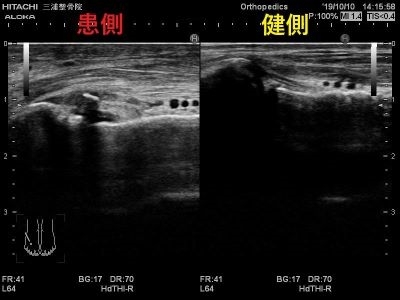

またここの損傷では

レントゲンには中々写りづらい

骨折が隠れていることも多いです。